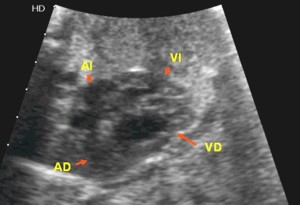

Coartación de aorta.

En principio esta malformación no es detectable de forma directa. Si se detectan signos indirectos de su existencia como es la dilatación del ventrículo derecho (ver figura y video de coartación). Se observa un ventrículo derecho desproporcionadamente mayor que el izquierdo.

Cuatro Cámaras, Coartación de aorta